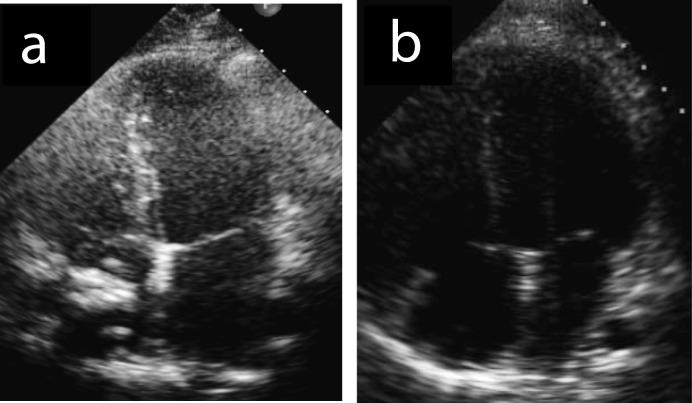

Catheter-related central thrombosis is a rare complication of long-term central line. We describe the case of an asymptomatic boy who was diagnosed a calcified thrombus in right atrium eight years after the removal of a long-term central venous device. Although the most appropriate therapeutic approach for managing floating right heart thrombi remains to be determined, surgical removal is an effective and safe procedure for calcified long-standing thrombus and it is to be preferred in elective conditions especially in young asymptomatic patients without hemodynamic involvement, that are at low risk of surgery-related morbidity and mortality.

导管相关的中心静脉血栓形成是长期中心静脉置管的一种罕见并发症。我们描述了一例无症状男孩的病例,该男孩在拔除长期中心静脉装置八年后被诊断出右心房有钙化血栓。尽管处理漂浮性右心血栓的最合适治疗方法仍有待确定,但手术切除对于钙化的长期血栓是一种有效且安全的方法,在择期情况下,尤其是对于没有血流动力学受累、手术相关发病率和死亡率风险较低的年轻无症状患者,手术切除是首选。